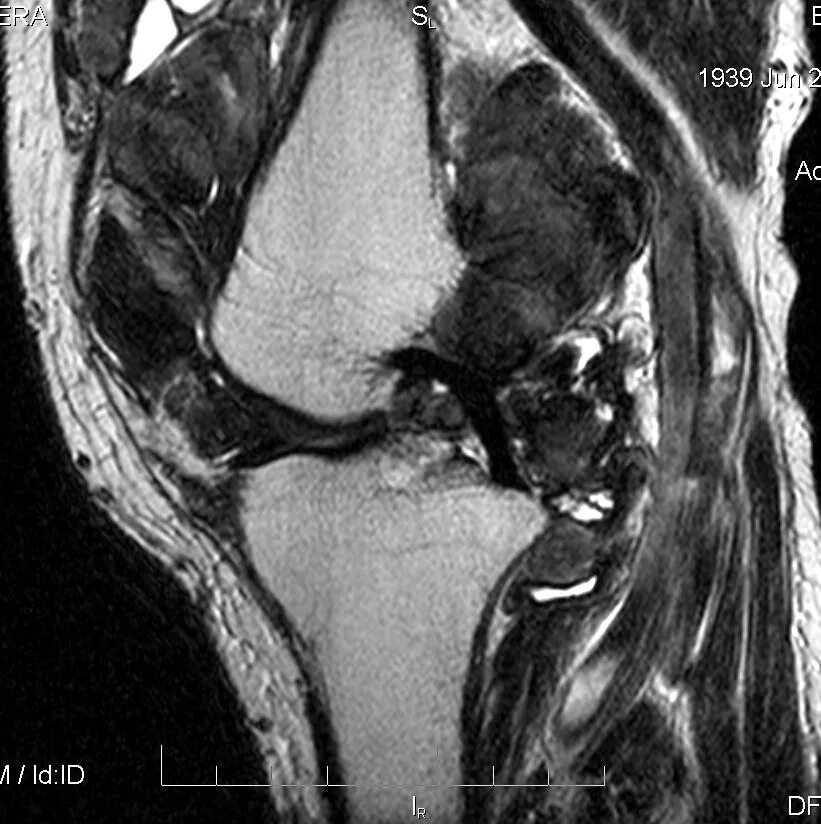

Пигментный виллонодулярный синовит